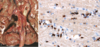

Los hallazgos característicos de la **encefalitis vírica** son manguitos de **linfocitos perivasculares** (A) y nódulos microgliales (B).